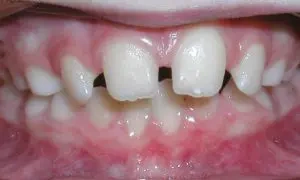

Spacing

Spacing problems may be caused by missing teeth, or they may only be a cosmetic or aesthetic issue.